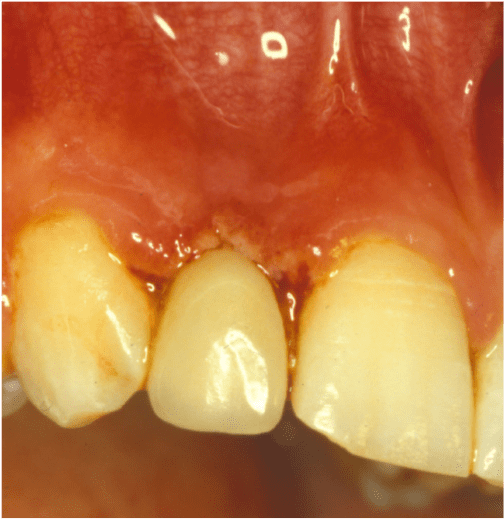

Recessione gengivale in paziente adulto

BlogGengive

Recessione gengivale

Read More